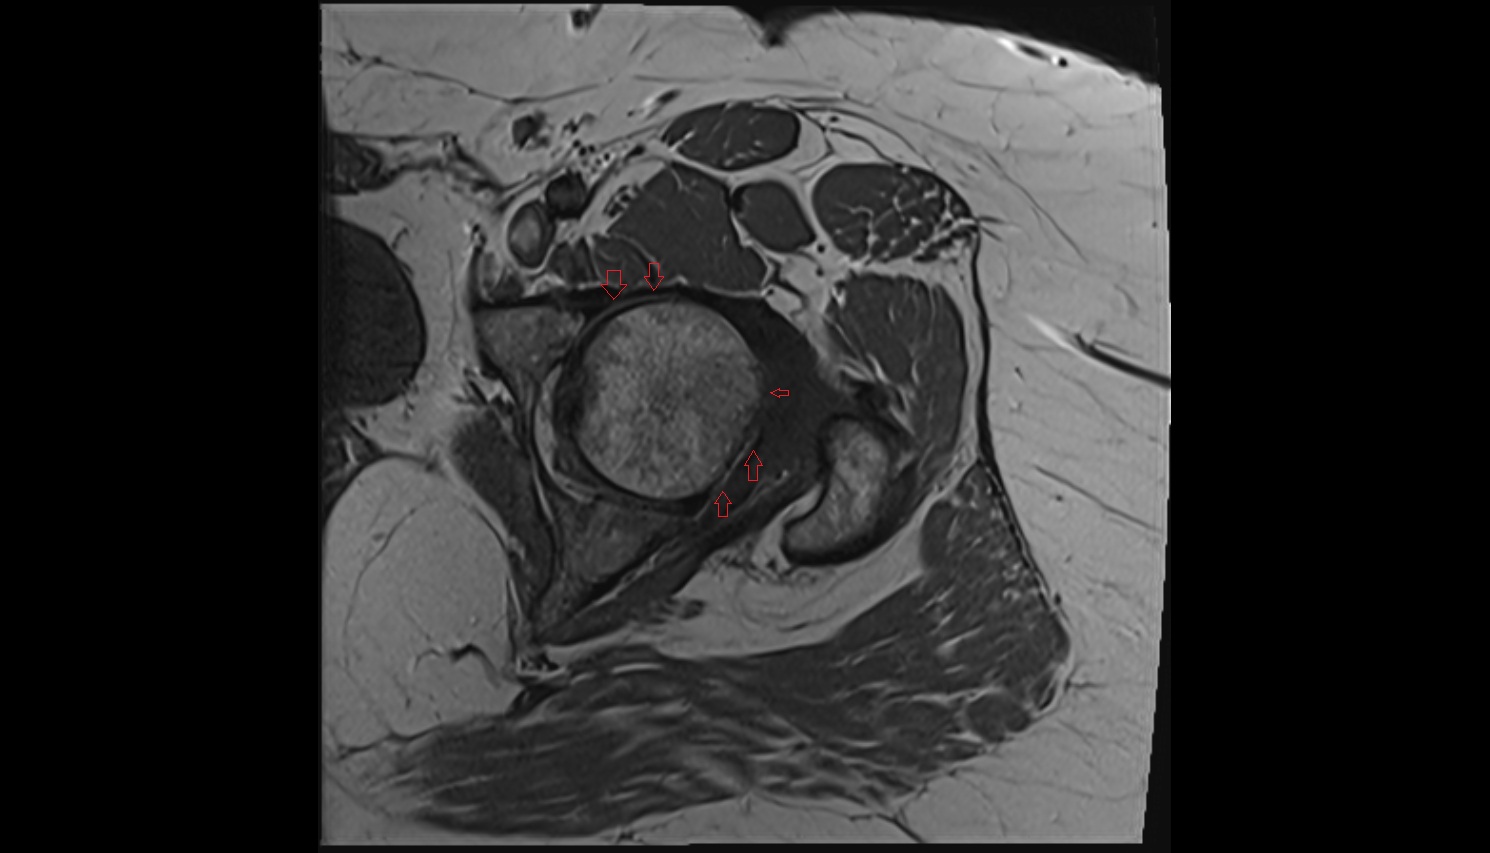

- Head of femur

- Hip joint

- Acetabular labrum

- Articular capsule of hip joint